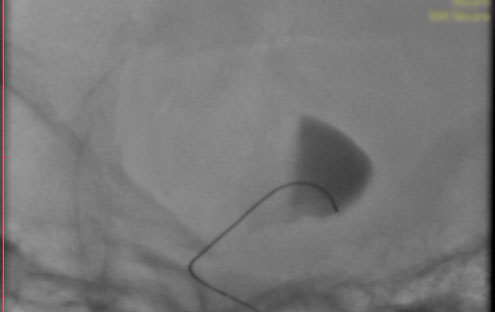

La paciente ingreso al Servicio de Hemodinamia el día martes 11 de febrero con un aneurisma cerebral gigante en la carótida izquierda y se le practicó una embolización; es decir una oclusión por dentro del mismo, donde se colocó un dispositivo denominado coils más un stent diversor de flujo. El procedimiento fue exitoso y contó con la colaboración de médicos neurointervencionistas del Instituto Oulton de la Ciudad de Córdoba.